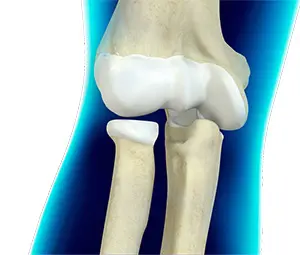

Elbow Anatomy

The elbow is a complex joint formed by the articulation of three bones – the humerus, radius, and ulna. The elbow joint helps in bending or straightening of the arm to 180 degrees and lifting or moving objects.